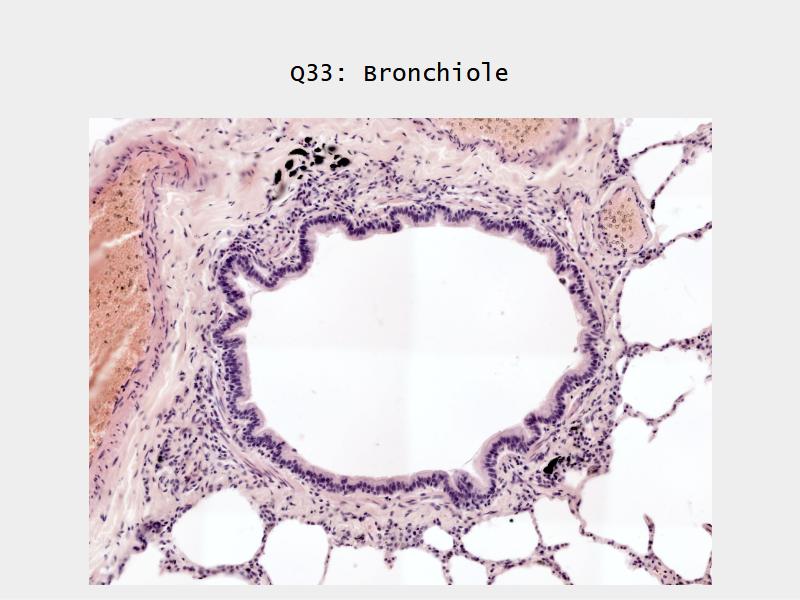

Bronchi - Transitions

- Intrapulmonary bronchi

- Irregular cartilage

- Respiratory epithelium

- Glands

- Bronchioles

- Smooth muscle REPLACE cartilage

- Ciliated columnar > Ciliated cuboidal

- NO glands - goblet cells -> secretory cells